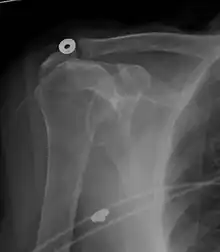

X-ray projectional radiography cannot directly reveal tears of the rotator cuff, a 'soft tissue', and consequently, normal X-rays cannot exclude a damaged cuff. However, indirect evidence of pathology may be seen in instances where one or more of the tendons have undergone degenerative calcification (calcific tendinitis). The humeral head may migrate upwards (high-riding humeral head) secondary to tears of the infraspinatus, or combined tears of the supraspinatus and infraspinatus.[47] The migration can be measured by the distance between:

- A line crossing the center of a line between the superior and inferior rims of the glenoid articular surface (blue in image).

- The center of a "best-fit" circle positioned over the humeral articular surface (green in image)

Normally, the former is positioned inferiorly to the latter, and a reversal is therefore indicating a rotator cuff tear.[47] Prolonged contact between a high-riding humeral head and the acromion above it, may lead to X-rays findings of wear on the humeral head and acromion and secondary degenerative arthritis of the glenohumeral joint (the ball and socket joint of the shoulder), called cuff arthropathy, may follow.[46] Incidental X-ray findings of bone spurs at the adjacent acromioclavicular joint may show a bone spur growing from the outer edge of the clavicle downwards towards the rotator cuff. Spurs may also be seen on the underside of the acromion, once thought to cause direct fraying of the rotator cuff from contact friction, a concept currently regarded as controversial.